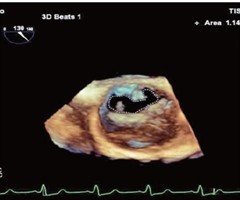

超声诊断胎儿右冠状动脉-右房瘘1例

[中图法分类号]R445.1;R714.5 [文献标识码]B 孕妇29岁,孕29周,孕2产0,因外院产前检查发现胎儿心脏结构异常来我院就诊。自诉孕前尿红细胞增多1年,未行特殊治疗;无心血管疾病家族史及遗传病史。产前常规超声检查:宫内单活胎,...